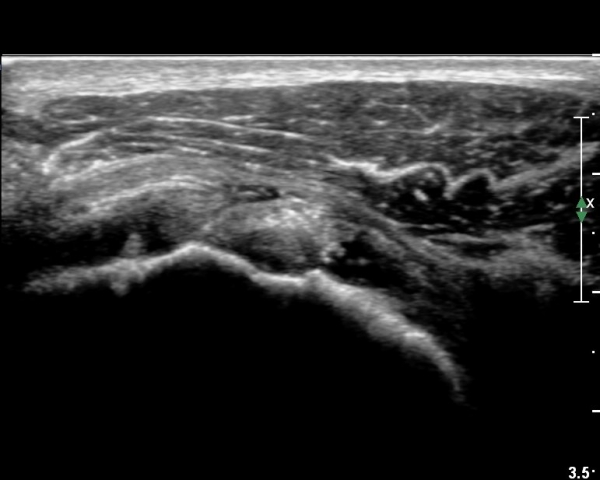

ÃÊÀ½ÆÄ ¼Ò°ß :  È¸Àü±Ù°³°£°Ý °Ë»ó»ó ±Ø»ê°ÇÀº Á¤»ó¼Ò°ßÀ» º¸À̳ª °ß°©ÇϱٰÇÀº Àú¿¡ÄÚ ¿¬°á¼º ¼Ò½ÇÀÌ

º¸¿© °ß°©ÇÏ±Ù°Ç ÆÄ¿­ÀÌ ÃßÁ¤µÈ´Ù(»çÁø 1). ŽÃËÀÚ¸¦ ¾à°£ ¾Æ·¡·Î À̵¿ÇÑ ÈÄ